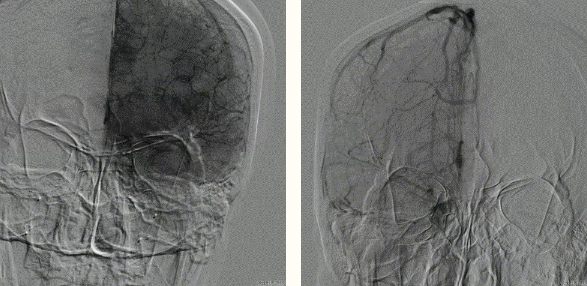

取出脑保护器、无血栓

术后左右脑血管造影一切正常